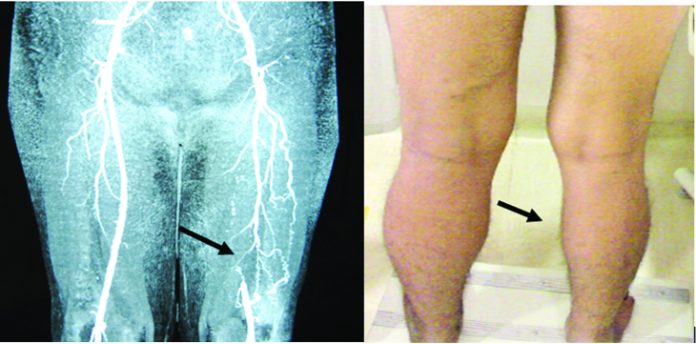

If you have problem of veins and it has increased enormously, laser or RFA (radiofrequency ablation) treatment is required. If leg artery is blocked, arterial bypass surgery is required. For all these procedures you should consult a Vascular or a Cardiovascular surgeon.

Diabetes, smoking and use of tobacco causes Permanent accumulation of blood clots in veins narrowing in blood pipes and decreased blood leading to night cramps in leg flow. This causes cramps in leg specially during night time.